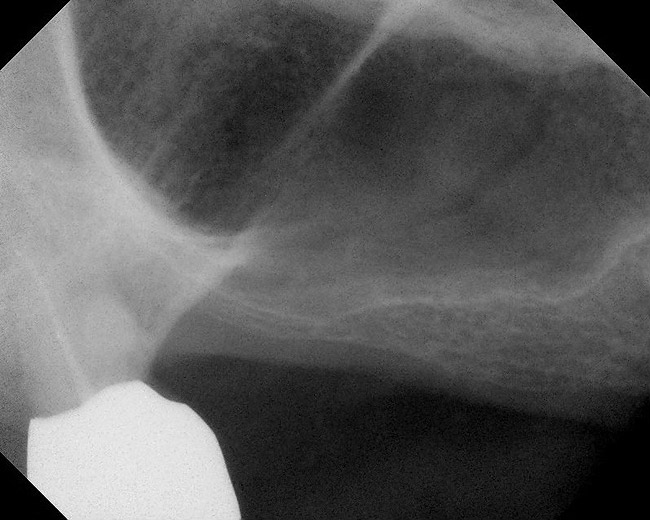

Figure 17  Preoperative radiograph showing ridge resorption.

Figure 17